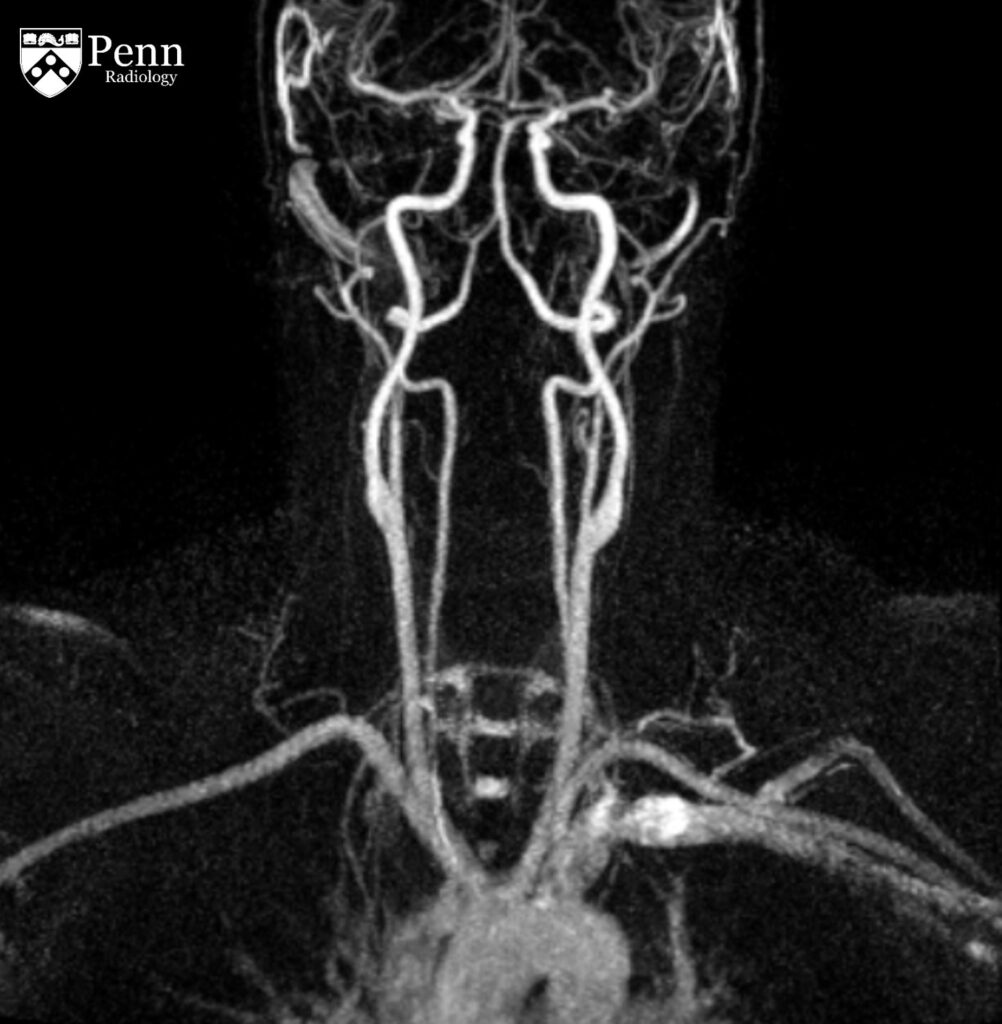

33-year-old woman after motor vehicle collision

A 33-year-old woman status post motor vehicle collision.